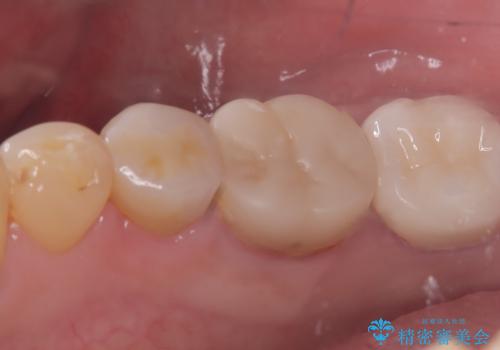

- 主訴:笑った時に下の銀歯が目立つので、白いものに替えたい

失活歯に保険適応のメタルクラウンがセットされていました。

根尖病巣と根管内に破折ファイルを認め、ファイル除去は困難だということをお伝えし、根管治療・土台・クラウンのやり替えとなりました。